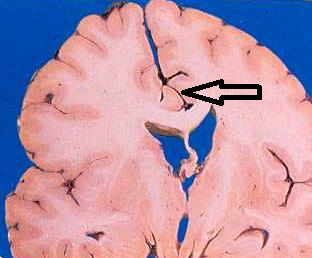

Trantentorial Uncal Herniation

Why is there CN 3 compression with pupillary dilation in a transtentorial uncal herniation?